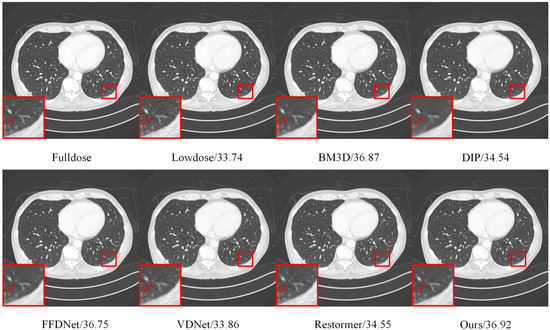

4.6. Real-Image Denoising